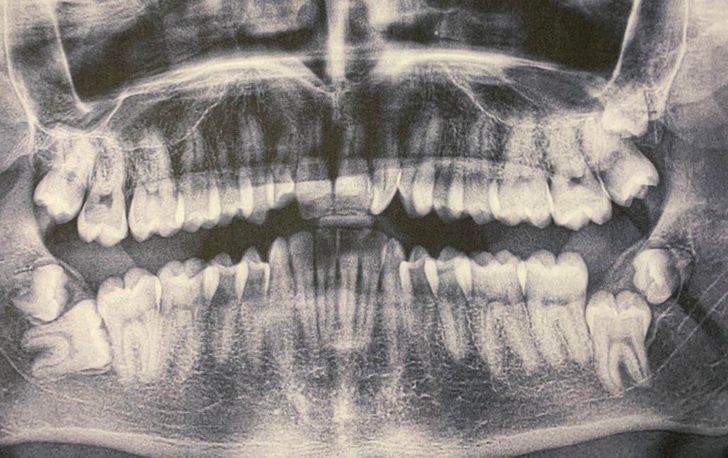

„Имам 7 осмици (вкупно 35 заби) “.